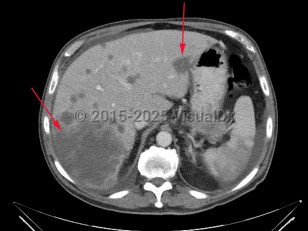

Liver cancer

Synopsis

There are several rare types of liver cancer. Angiosarcoma and epithelioid hemangioendothelioma arise from mesenchymal cells. Intraductal papillary neoplasm and mucinous cystic neoplasm with invasive carcinoma arise from the bile ducts.